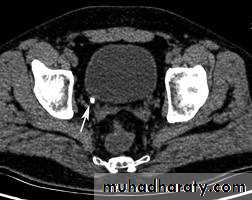

CT scans used in some hospitals during acute renal stone-Non contrast CT sensitively identify calculi and non opacified collecting system down to the level of obstruction. it has a sensitivity of 97% and specificity of 96% for detection of ureteral calculi

-Over 90% of calculi are radiopaque on plain films and virtually all on CT as very sensitive for detection of calculi, even those that appear radiolucent on plain film.

-Only pure uric acid and xanthine stones are radiolucent on plain x-ray but CAN be identified by CT or US, uric acid stones are associated with increased uric acid excretion in urine as in gout.